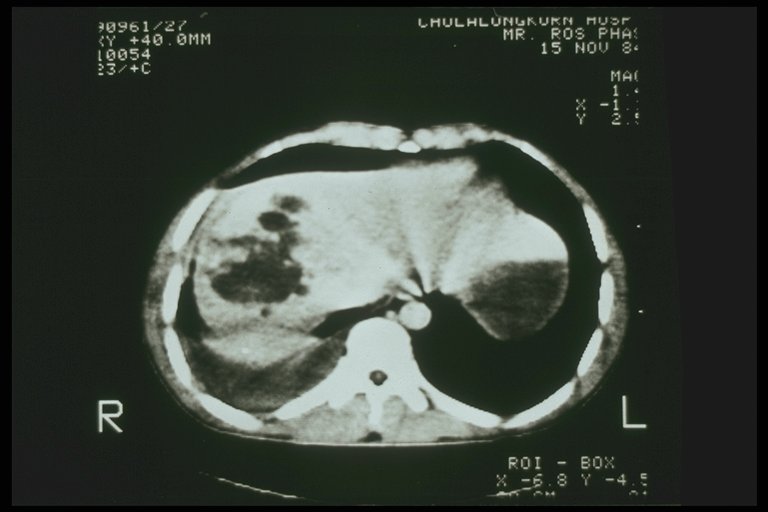

Severe liver injury with intrahepatic hematoma

Severe liver injury, multiple laceration over the right lobe are noted from CT scan

Combined severe liver injury and splenic hematoma, intraperitoneal bleeding is also noted